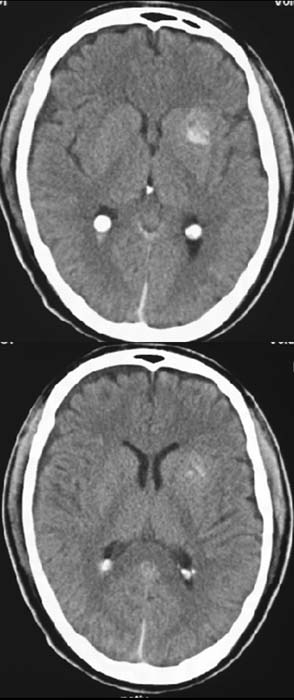

CCT nativ (ohne Kontrastmittel).

Hyperdense

(60-80HE) Raumforderung links im Bereich des Linsenkerns.

Kleine,

typische Stammganglienblutung links